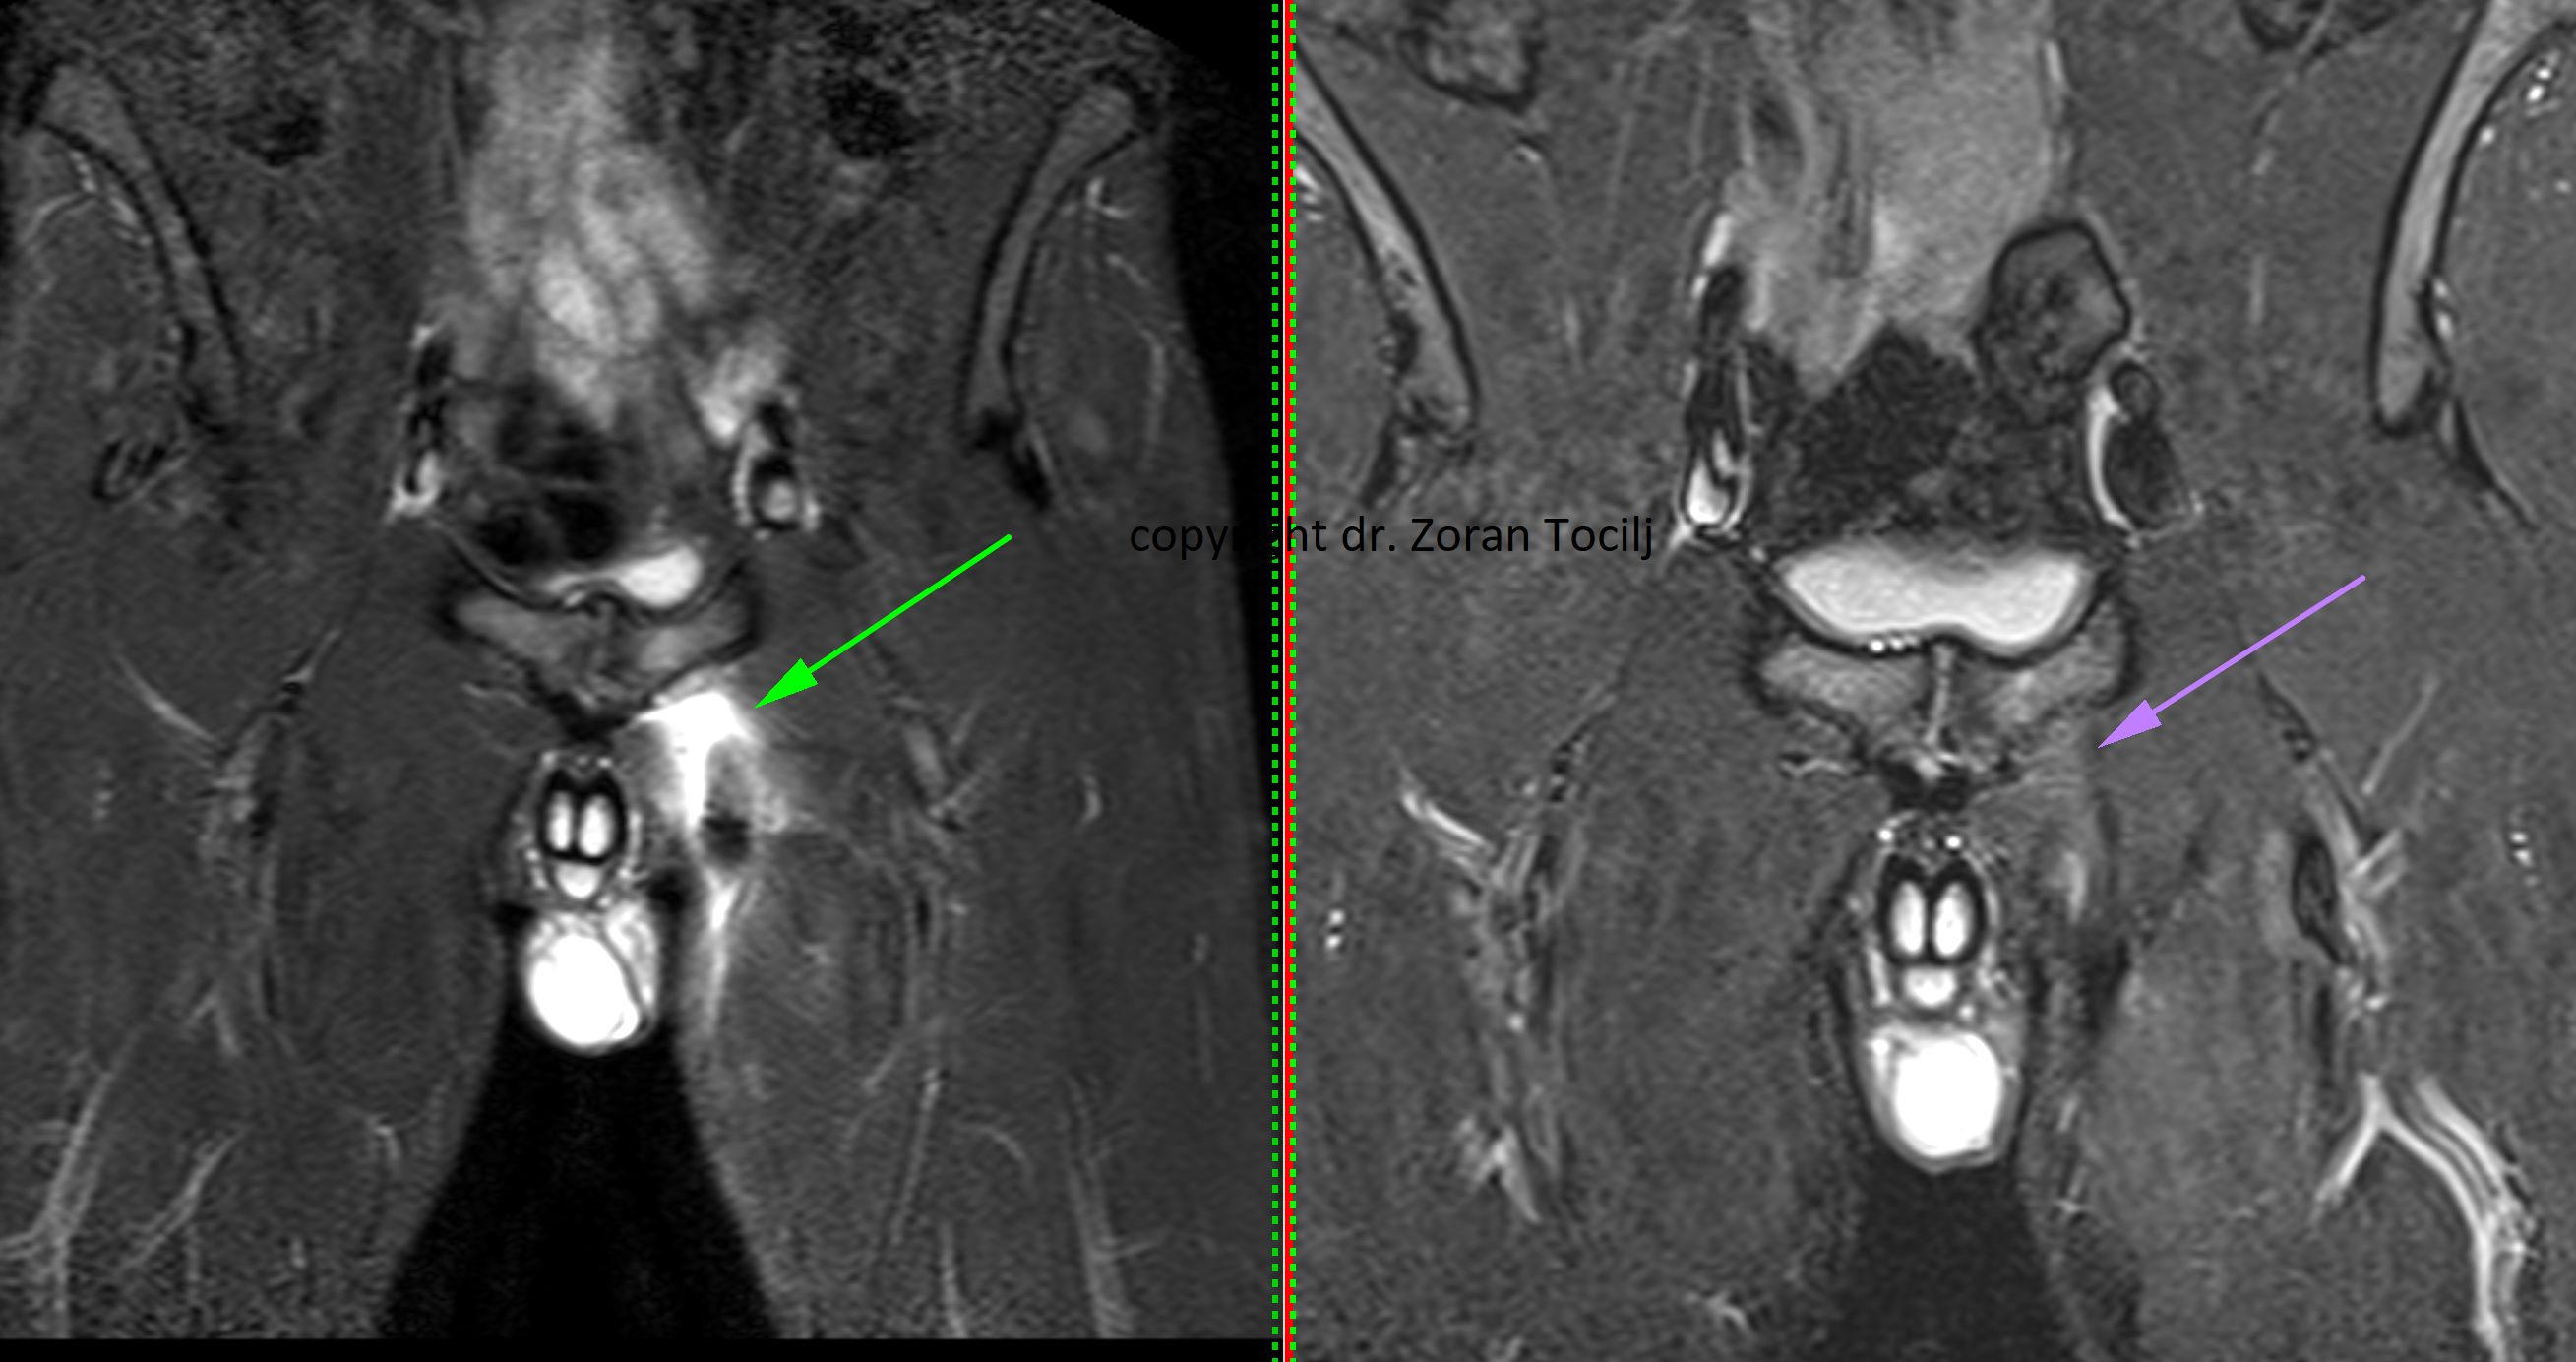

Hip bone edema treatment

ACL REGENERATION TREATMENT

ACL regeneration

Specialized treatment combination of prolotherapy, vitamins, amino acids  and bisphosphonates help heal bone contusions, stress fractures or postoperative bone edema. Therapies also stabilize knee bone osteoarthritis. MRI picture before therapy (left) and 7 weeks after (right).